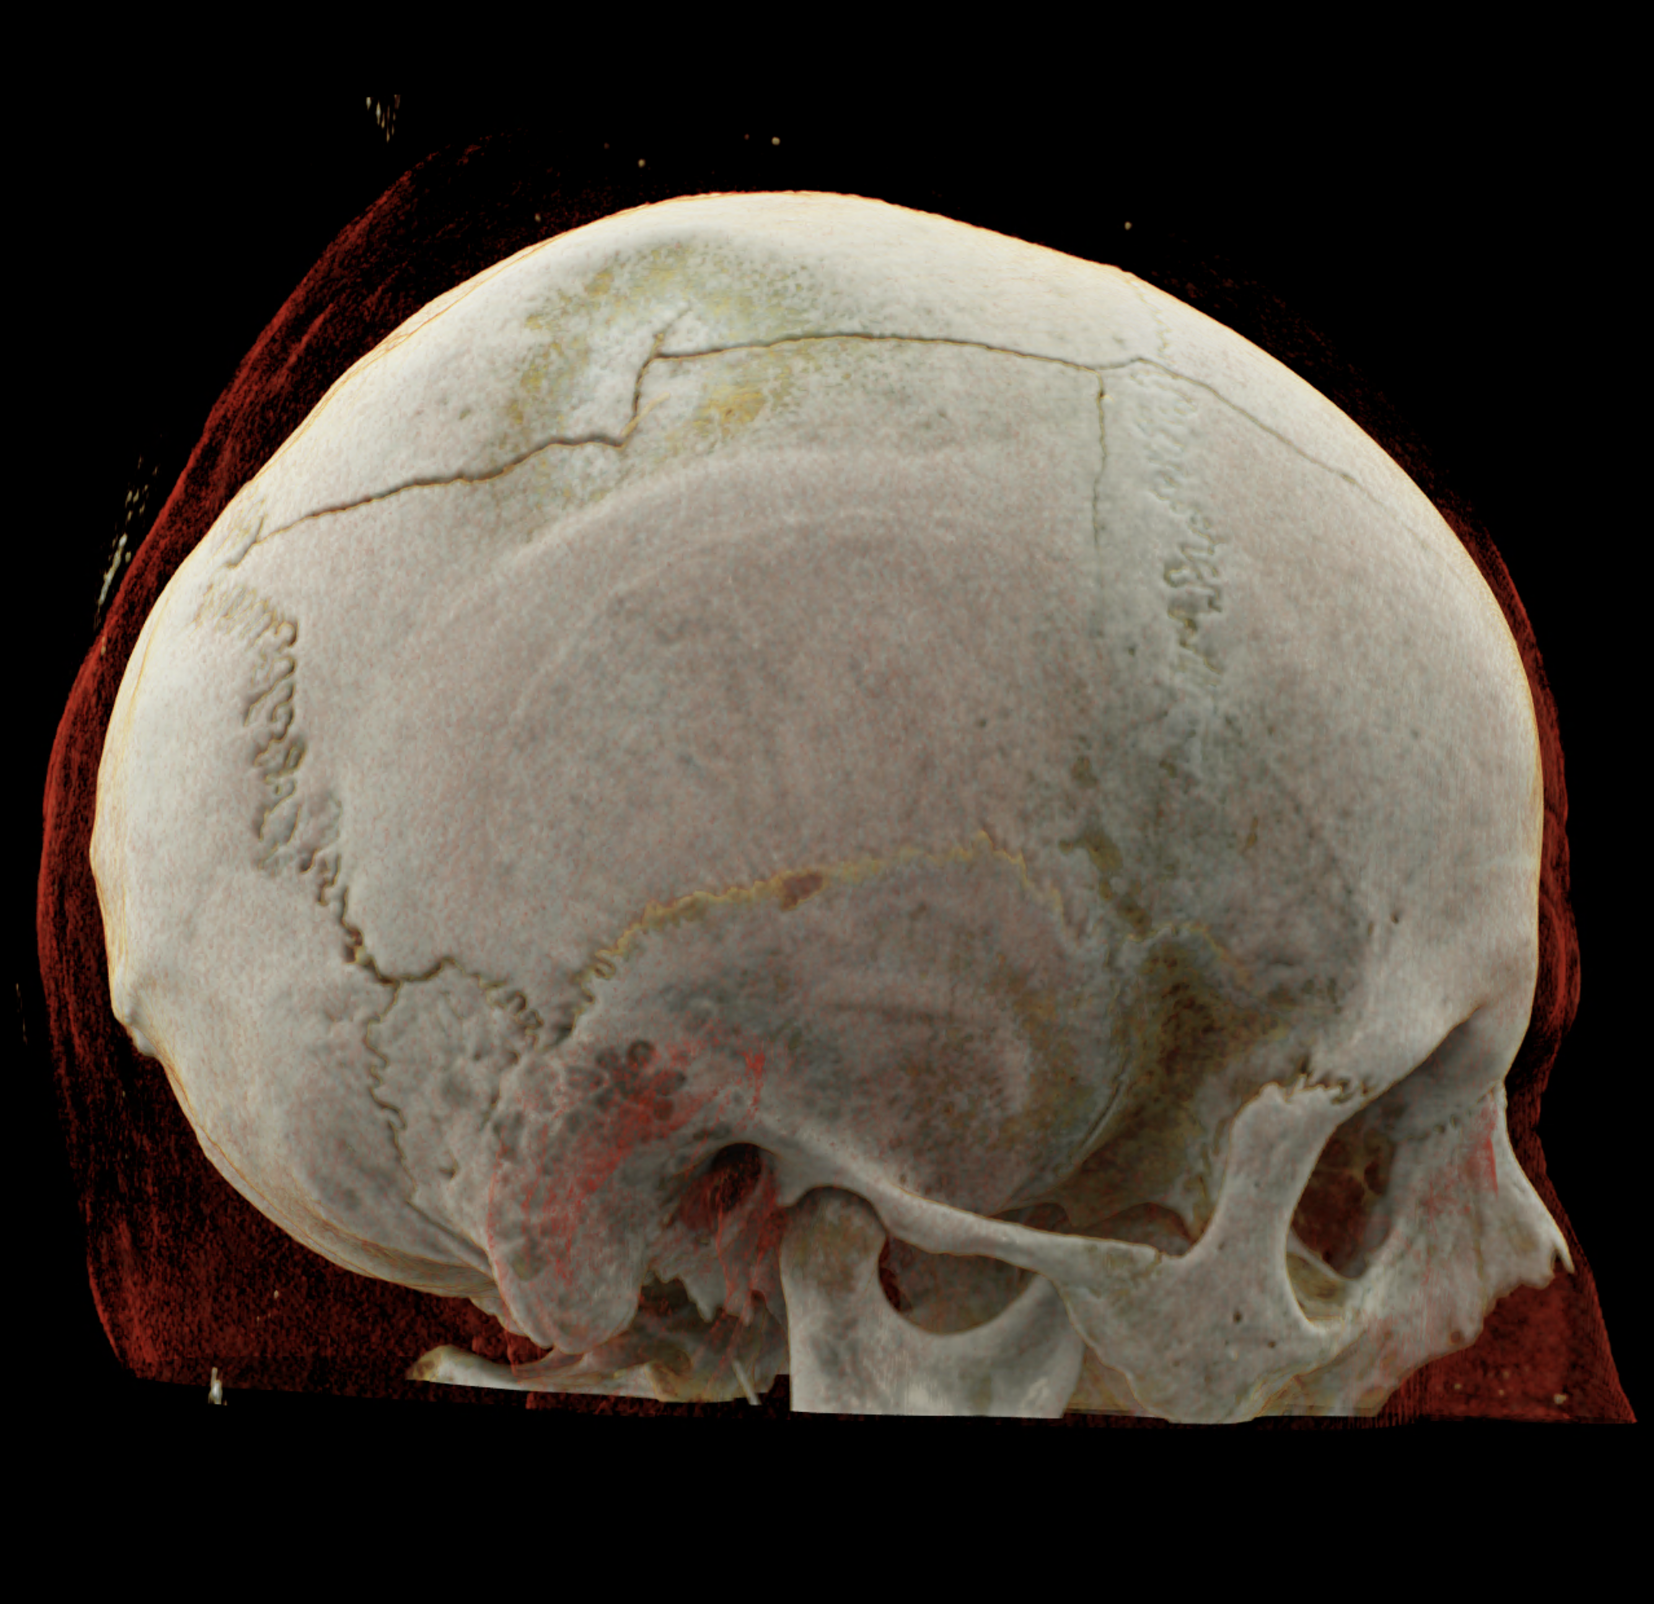

Three-dimensional reconstructions also show a complex skull fissure that extends from the frontal bone to the parietal and temporal bones.

volume rendered technique – display of the fissure course